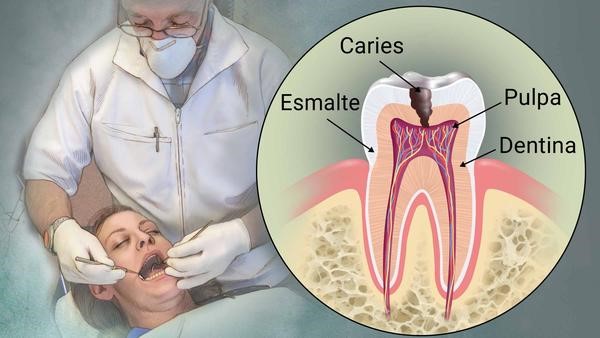

¿Qué es Caries dental?

La caries es el daño que le ocurre a un diente cuando las bacterias que se encuentran en la boca producen ácidos y estos atacan a la superficie del diente (esmalte), produciendo un pequeño agujero en el diente llamada caries, que, si no se tratan a tiempo, puede llegar a afectar las capas internas del diente (dentina y pulpa), causando dolor, infección e incluso la pérdida del diente.

Síntomas de la caries

Diagnóstico de la caries

Tratamiento de la caries